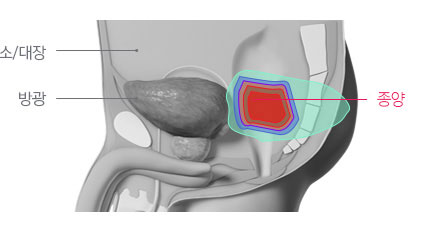

수술이 쉽지 않은 재발 직장암에서 수술 전후 고선량 방사선치료를 위해 적용될 수 있습니다.

이미 방사선치료를 시행한 적 있는 재발 직장암의 경우 우선 고려될 수 있습니다.

양성자치료는 방사선 재 치료 또는 고선량 치료로 인한 부작용에 대한 우려를 낮추면서 충분한 방사선량을 전달하여 높은 종양 제어율을 얻을 수 있습니다.

이미 방사선치료가 시행된 재발 직장암의 경우 종양 제거가 어렵고, 수술의 경우 미용적, 기능적 제한이 큰 것으로 알려져 있습니다. 따라서 고선량의 방사선 재 치료가 시행되는 경우가 많은데, 이 경우 세기조절 방사선치료를 시행하더라도 주변 정상 장기에 노출되는 방사선으로 인한 부작용이 흔하며, 총 방사선량이 제한되어 5년 종양 제어율이 50% 이하로 알려져 있습니다. 하지만 주변 정상 장기에 방사선 노출을 크게 낮출 수 있는 양성자치료는 부작용에 대한 우려를 낮추면서 고선량의 방사선을 전달하여 종양을 제거할 수 있을 것으로 기대하고 있습니다.

직장암 환자에서 양성자치료에 대한 임상 결과는 아직 드문 상황입니다. 하지만 양성자치료와 유사한 특성을 가진 입자선 치료 결과를 보면 90% 이상의 장기 종양 제어율이 보고된 바 있습니다.